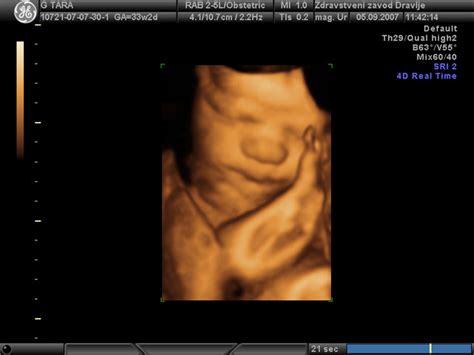

Izraža se z obrazno mimiko: Z opazovanjem 4D ultrazvočne slike so britanski znanstveniki ugotovili, da se plod v 24. tednu starosti že lahko smeje, pri 36. tednu starosti pa se lahko izraža skozi obrazne kretnje in dela različne mimike obraza od spusta obrvi do namrščenega noska in širokega nasmeha. Dojenčki v maminem trebuhu pa tudi pogosto sesajo svoj prst in tudi zehajo. Po 32. tednu na 4D ultrazvoku pogosto opazimo nasmeh, sesanje palca, odpiranje oči. Večina teh gibov je refleksnih. Dojenčki se smejijo in jokajo. Starši včasih dobijo fantastično sliko iz ultrazvoka, na kateri je otrok videti, kot da se smeji. Britanski znanstveniki so potrdili, da se dojenčki res smejijo, lahko pa se tudi namrščijo, nagubajo nos ali dvignejo obrvi. Poleg tega, da se smejijo, naj bi dojenčki tudi jokali. Raziskave so pokazale, da nizkofrekvenčni hrup, usmerjen na trebuh, kjer je plod, v tretjem trimesečju, povzroči vedenje, ki je videti kot jok. Otrok odpre usta, nepravilno diha, znanstveniki pa so opazili celo trepetanje ustnic.